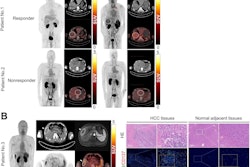

Also, in the area of radiotracer development, we posted a story about a new immuno-PET tracer that shows promise in patients with liver cancer and another on a tracer in development for detecting primary tumors, involved lymph nodes, and distant metastases in patients with clear cell renal cell carcinoma.